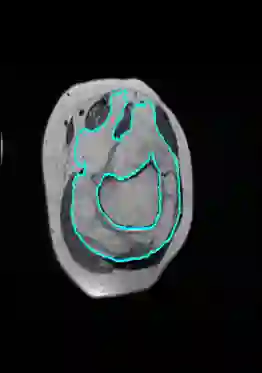

Radiomics uses quantitative medical imaging features to predict clinical outcomes. Currently, in a new clinical application, finding the optimal radiomics method out of the wide range of available options has to be done manually through a heuristic trial-and-error process. In this study we propose a framework for automatically optimizing the construction of radiomics workflows per application. To this end, we formulate radiomics as a modular workflow and include a large collection of common algorithms for each component. To optimize the workflow per application, we employ automated machine learning using a random search and ensembling. We evaluate our method in twelve different clinical applications, resulting in the following area under the curves: 1) liposarcoma (0.83); 2) desmoid-type fibromatosis (0.82); 3) primary liver tumors (0.80); 4) gastrointestinal stromal tumors (0.77); 5) colorectal liver metastases (0.61); 6) melanoma metastases (0.45); 7) hepatocellular carcinoma (0.75); 8) mesenteric fibrosis (0.80); 9) prostate cancer (0.72); 10) glioma (0.71); 11) Alzheimer's disease (0.87); and 12) head and neck cancer (0.84). We show that our framework has a competitive performance compared human experts, outperforms a radiomics baseline, and performs similar or superior to Bayesian optimization and more advanced ensemble approaches. Concluding, our method fully automatically optimizes the construction of radiomics workflows, thereby streamlining the search for radiomics biomarkers in new applications. To facilitate reproducibility and future research, we publicly release six datasets, the software implementation of our framework, and the code to reproduce this study.